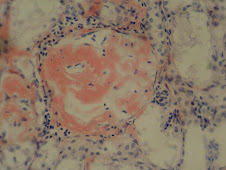

Microscópicamente: sustancia amorfa, hialina, eosinófila (H/E),rodea vasos sanguíneos y atrofia tejidos adyacentes por compresión

Refractario a muchos colorantes, Rojo Congo +, birefringencia verde con luz polarizada